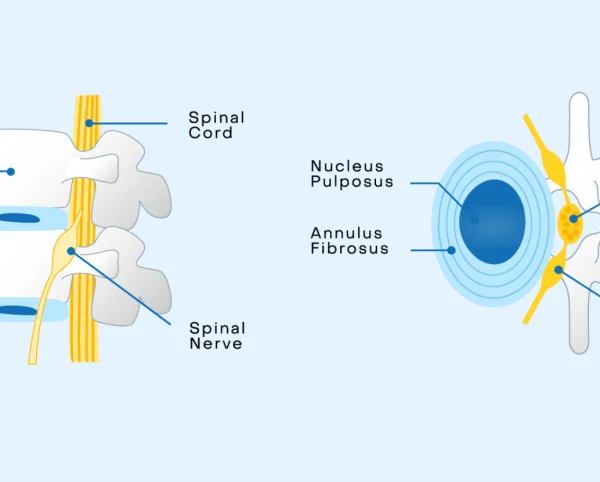

He is dedicated to providing personalized treatment plans for conditions such as back pain, slipped disc, sciatica, spinal stenosis, cervical and lumbar spine disorders, and degenerative spine diseases. Dr. Agrawal combines modern medical technology with a compassionate approach, focusing on accurate diagnosis and patient education at every step.

Non-Surgical Disc Prolapse Pain Management

Sciatica / Lumbar Disc Prolapse Treatment